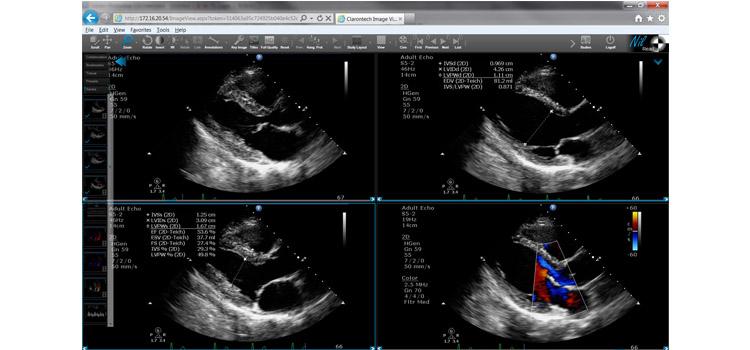

This is a tutorial video on how to perform an artificial intelligence (AI) automated cardiac ejection fraction ...

July 2, 2019 — DiA Imaging Analysis has partnered with Konica Minolta Healthcare Americas Inc. to expand analysis ...

June 19, 2019 — DiA Imaging Analysis announced the presentation of two studies assessing the performance and accuracy of ...

April 9, 2019 — DiA Imaging Analysis announced the launch of LVivo SAX, a cardiac analysis tool that helps clinicians ...

June 27, 2018 – A recent study conducted with the Minneapolis Heart Institute found that Bay Labs’ EchoMD AutoEF deep ...

June 19, 2018 – Cardiovascular imaging artificial intelligence (AI) company Bay Labs announced its EchoMD AutoEF ...